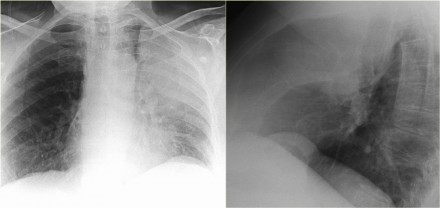

胸疾病胸片表现之肺不张

肺不张胸片表现

肺不张x线表现

肺不张胸片典型图片

肺不张胸片表现图片